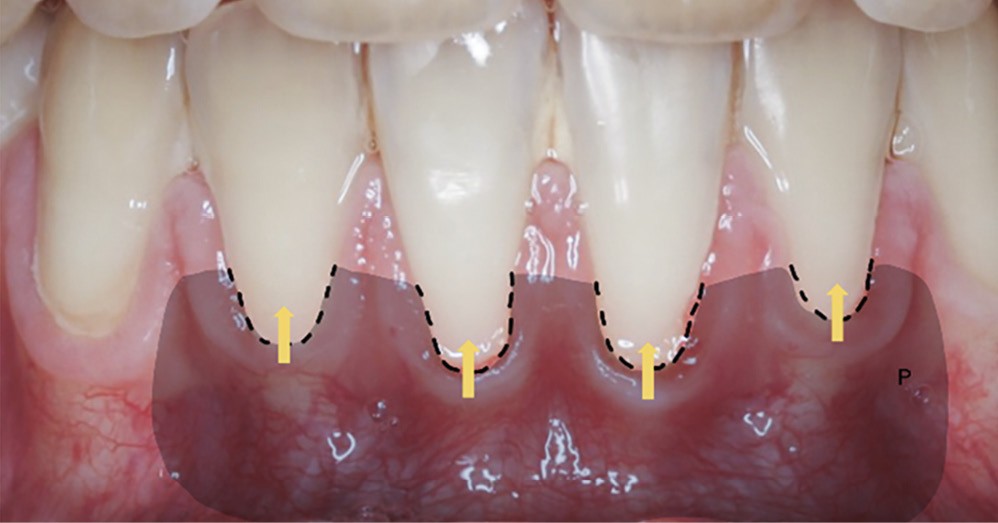

La récession RT1 est une récession sans perte d’attache interproximale et où la JAC est cliniquement non détectable en zone interproximale, le recouvrement complet est possible. Lorsque la perte d’attache interproximale est inférieure ou égale à la perte d’attache vestibulaire, on parlera de récessions RT2, le recouvrement ne sera que partiel. La récession RT3 est une récession où la perte d’attache interproximale est supérieure à la perte d’attache vestibulaire, dans ce cas-là le recouvrement est impossible. Il est important aussi de savoir identifier et distinguer la récession gingivale de l’éruption passive incomplète qui est une anomalie de développement de l’éruption dentaire (fig. 1).

La greffe épithélio-conjonctive (GEC) [7, 8] consiste au remplacement du tissu parodontal existant par un greffon épithélio-conjonctif dont l’indication principale est l’augmentation en hauteur et en épaisseur du tissu kératinisé (fig. 2). Elle peut aussi être utilisée dans le recouvrement radiculaire (avec des résultats en termes de recouvrement inférieurs à ceux des techniques de greffe de conjonctif enfouie), l’aménagement des crêtes édentées, l’aménagement péri-implantaires [9, 10] (fig. 3), ou en association avec un traitement ortho-parodontal [11]. Le principal défaut de cette technique est son aspect inesthétique ; elle sera donc réservée à des zones non visibles comme les incisives mandibulaires ou les zones postérieures.